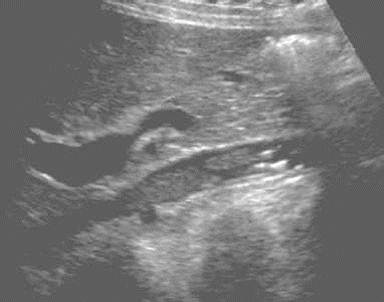

IVC Thrombosis

IVC Tumor